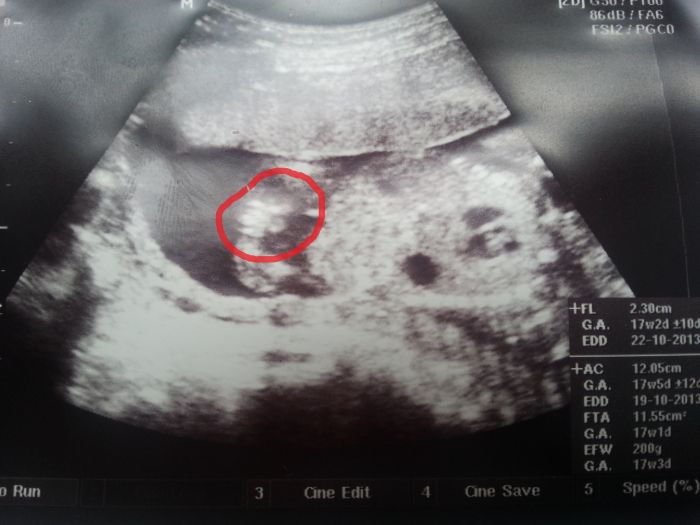

Zdravím holky, poraďte, je to holka, nebo kluk??? pan doktor se přiklání k holčině

18 TT